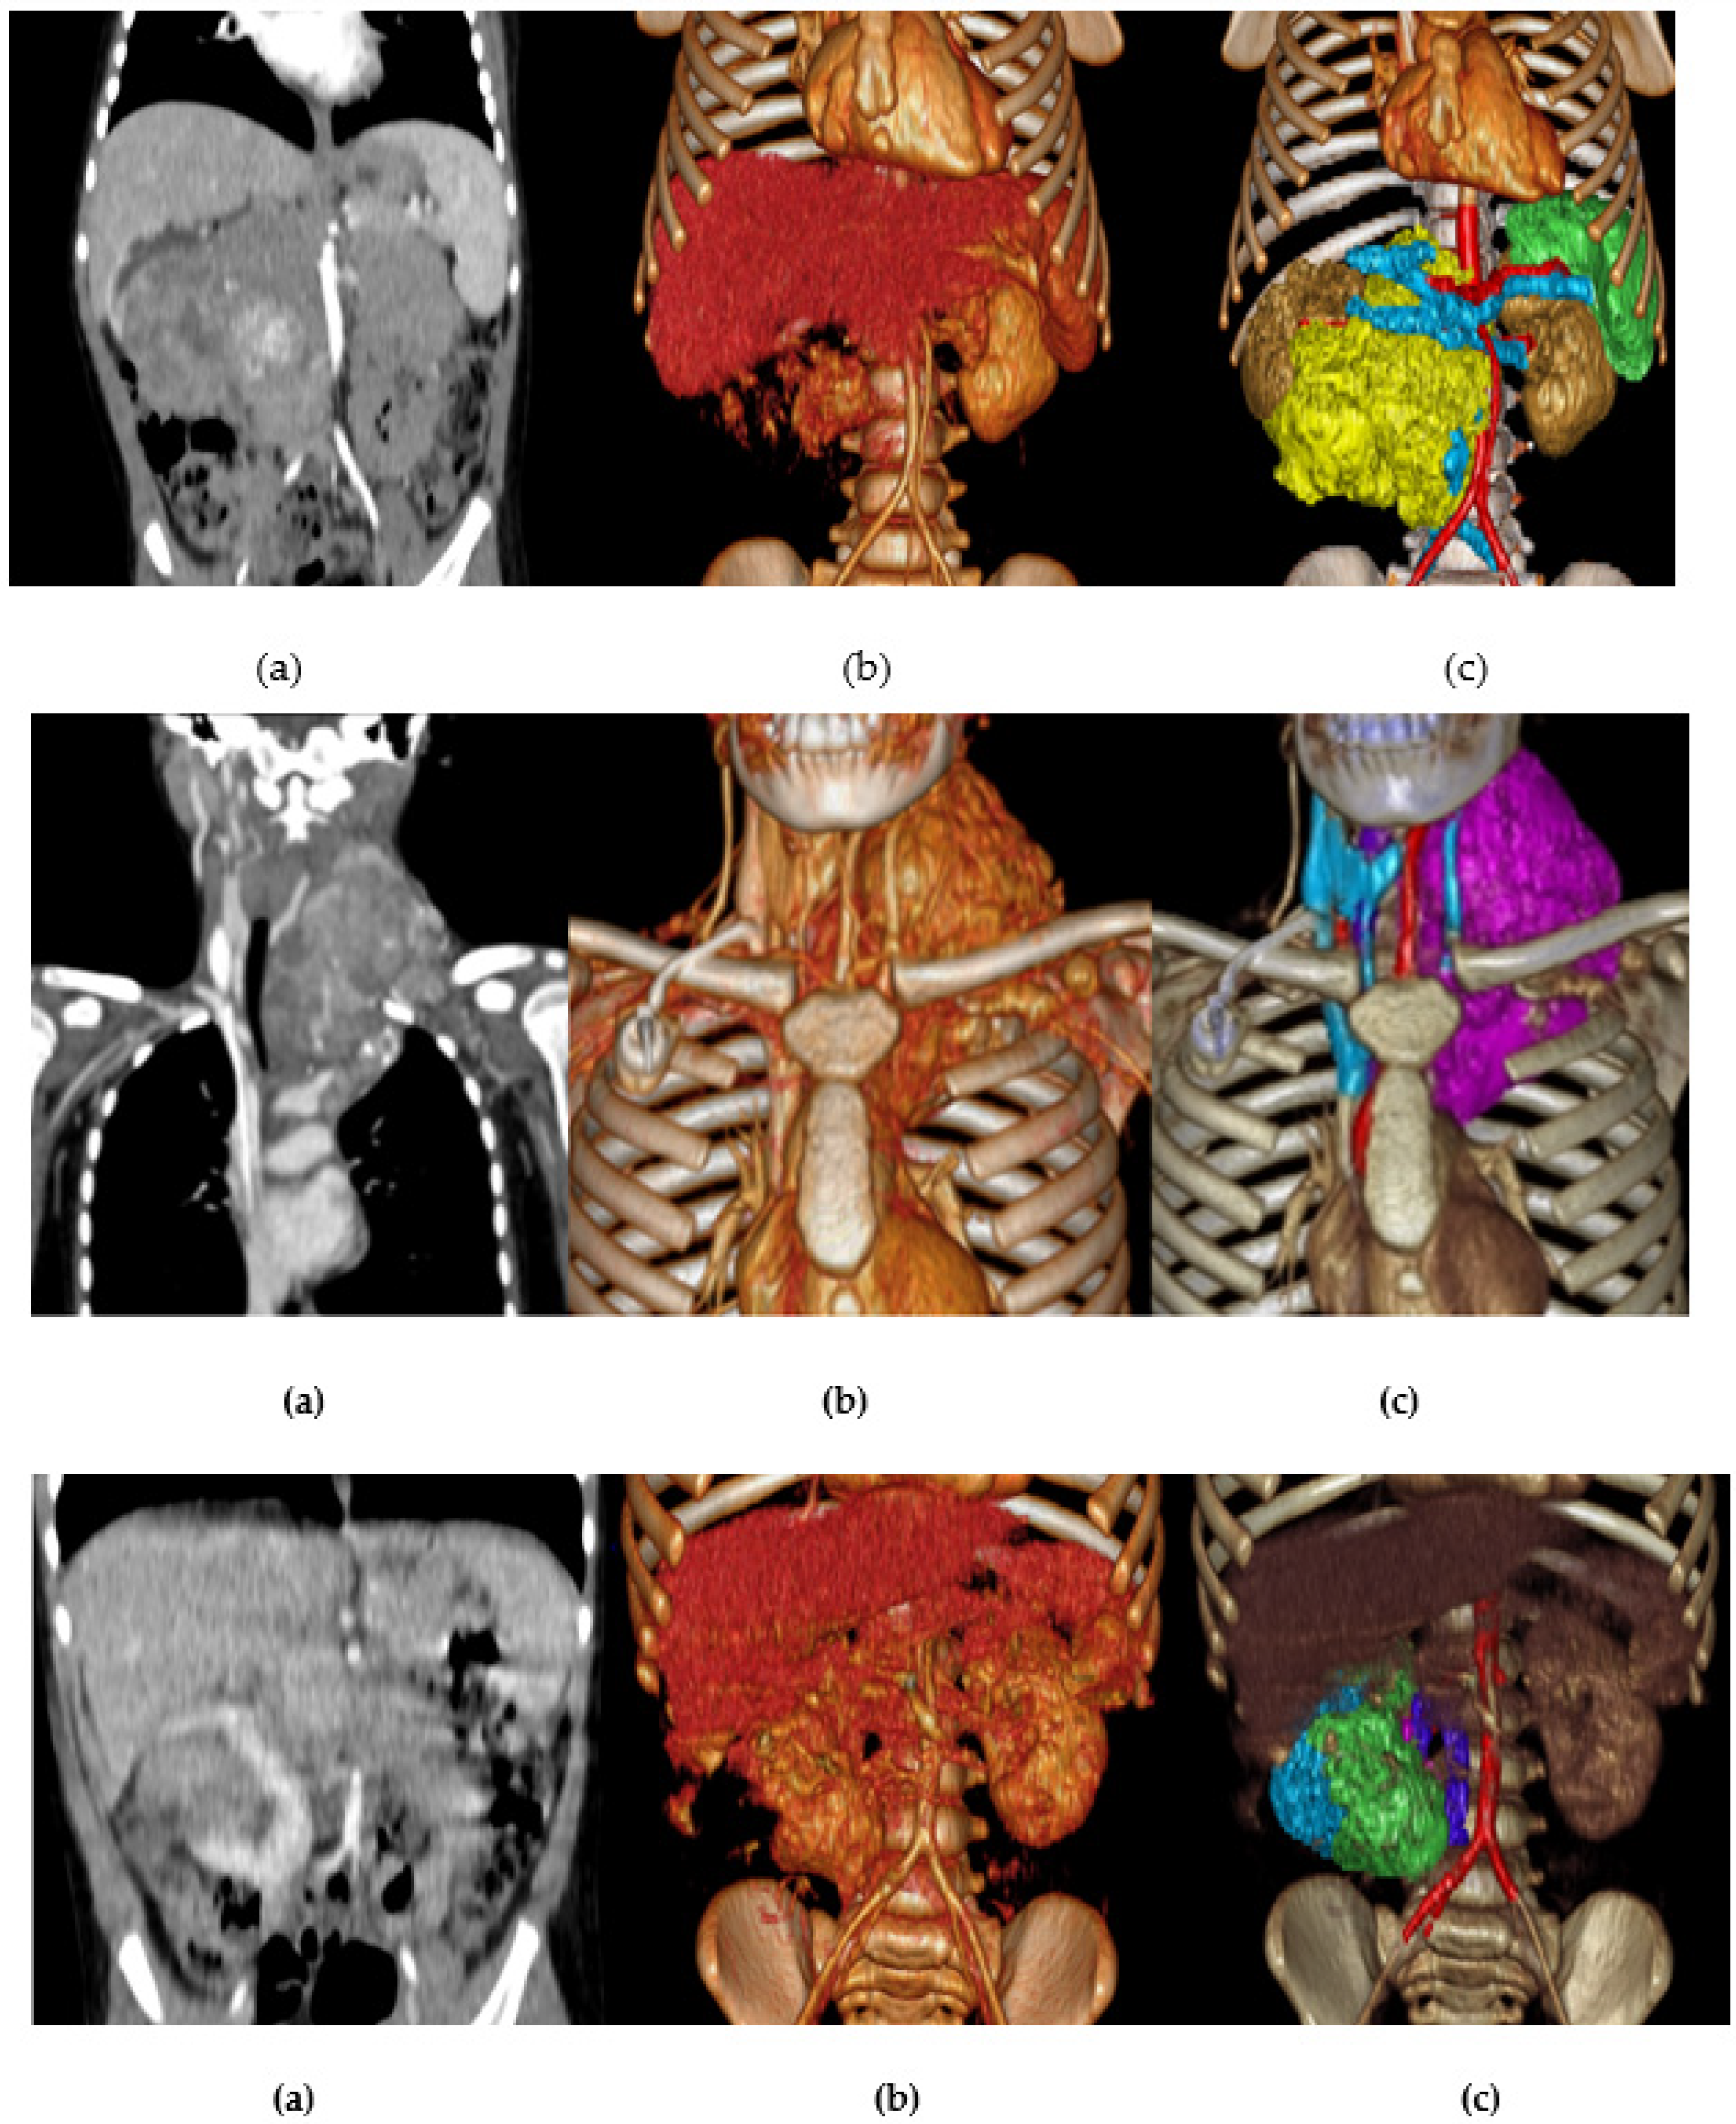

3.1.1. Two-Dimensional Projection Renderings

3.1.2. Volume Rendering and Cinematic Rendering

3.1.3. Three-Dimensional Virtual Simulations (CAD Models)